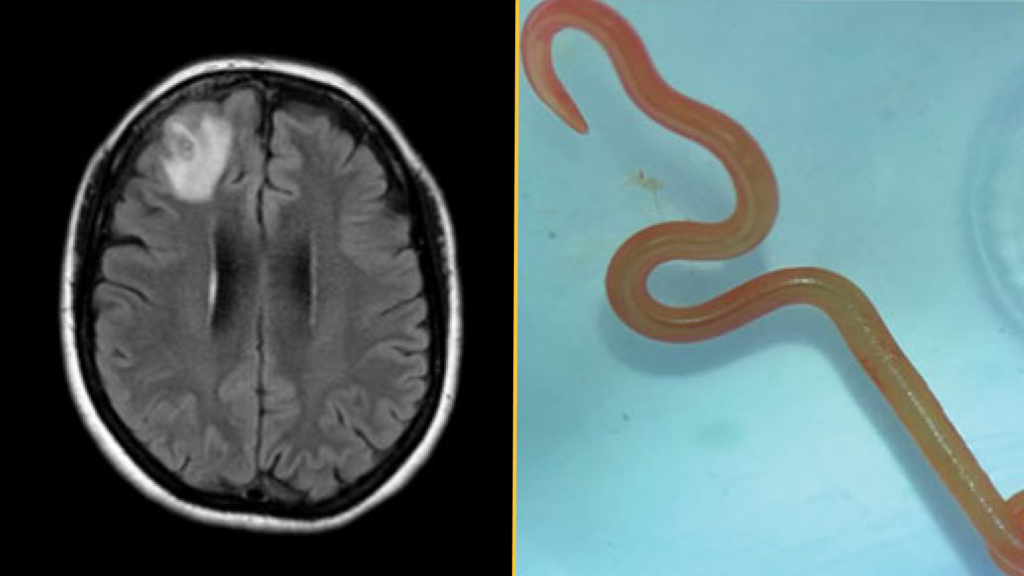

The diagnosis: About a year after her initial hospital visit, the woman began to develop signs of depression and had episodes of forgetfulness. Physicians ordered an MRI of her brain and detected a lesion on the right frontal lobe. They then performed an open biopsy to expose and examine the damaged area. That’s when they discovered “a stringlike structure” inside the lesion, which they identified as a living parasitic worm called a helminth, according to a report of her case.

The worm was bright red and measured about 3 inches (80 millimeters) long and 0.04 inches (1 millimeter) thick.